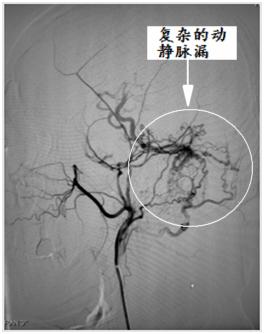

脑病介入科曹骅主任、赵宏廷主治医师先进行左侧颈外动脉血管造影,以明确复杂瘘口,术前造影:颈外动脉中包括枕动脉、耳后动脉、颞浅动脉的多个分支通过硬脑膜向颅内静脉形成异常引流,栓塞术难道很大。

手术过程:术中采取弹簧圈辅助填塞,Onyx液态胶多支供血动脉分次栓塞治疗措施,由于供血动脉纵横交错,手术难道可想而知,经过4小时的艰难努力,于18:30手术结束,术程顺利,成功帮助患者填塞了动静脉瘘,为患者解决了病痛。